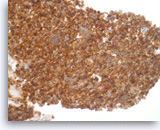

Pancreatic endocrine neoplasm #1,

Pancreas FNA, Cell Block.

The synaptophysin immunostain shows cytoplasmic positivity in the tumor cells, indicative of neuroendocrine differentiation.

40X

Pancreatic endocrine neoplasm #1,

Pancreas FNA, Cell Block.

The synaptophysin immunostain shows cytoplasmic positivity in the tumor cells, indicative of neuroendocrine differentiation.

40X